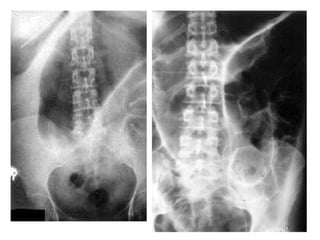

Investigations:

• Radiographs are essential to confirm the diagnosis

and accurate the site of the obstruction.

• The radiological diagnosis is based on a

supine(erect) abdominal radiograph.

• If conditions of the patient are poor a lateral

decubitus position view may be taken.

• Usually can determine whether small bowel, colon

or both are distended.

• Radiographs show multiple gas-fluids levels, with

distended bowell resembling an inverted U.

• Obstruction of the small bowel outlines the valvulae

conniventes, which occupy the entire transverse

diameter of the bowel image.

• Small bowel pattern occupies the more central portions

of the abdomen.

• Large bowel obstruction shows haustral markings, that

occupies only a portion of the transverse diameter of

the bowel, unlike valvulae conniventes, are spaced

irregularly and the indentations are not placed

opposite one another.

• Large bowel pattern occupies the periphery or pelvis

portion of the abdomen.

• A distended caecum is shown by a rounded gas shadow

in the right iliac fossa.

• Large bowel obstruction with competent ileocecal valve

show colon distention and little small bowel gas.

• Large bowel obstruction with incompetent ileocecal

valve shows small and large bowell distention and fluids

levels.